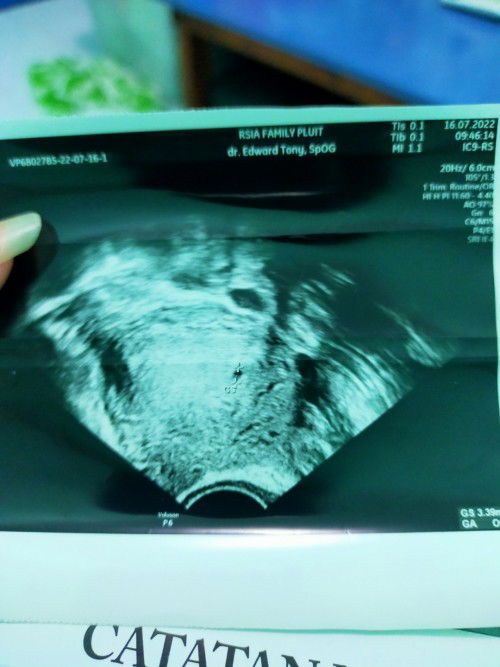

Apakah ini sudah ada janinnya? Atau masih kantung?

Hy mommies.. Aku masih newbie banget disni. Mau tanya dong apakah hasil usg aku ini normal untuk kehamilan 6 minggu. Kmren dokter bilang kantungnya br berusia 4 minggu. Koq bisa beda gitu ya mommies. Ad yg pernah gini juga ga?